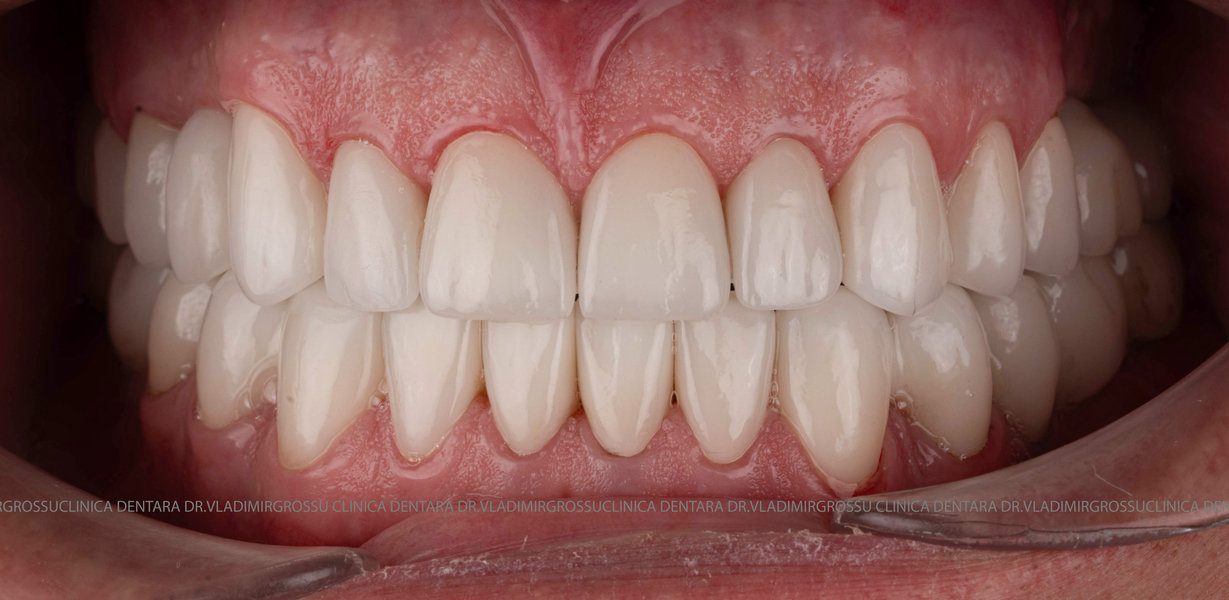

- Estetică superioară – imită perfect dinții naturali

- Funcționalitate completă – mestecare și vorbire fără restricții

- Coroane din zirconiu sau ceramică integrală

- Materiale premium – zirconiu, ceramică E-max, titan pur